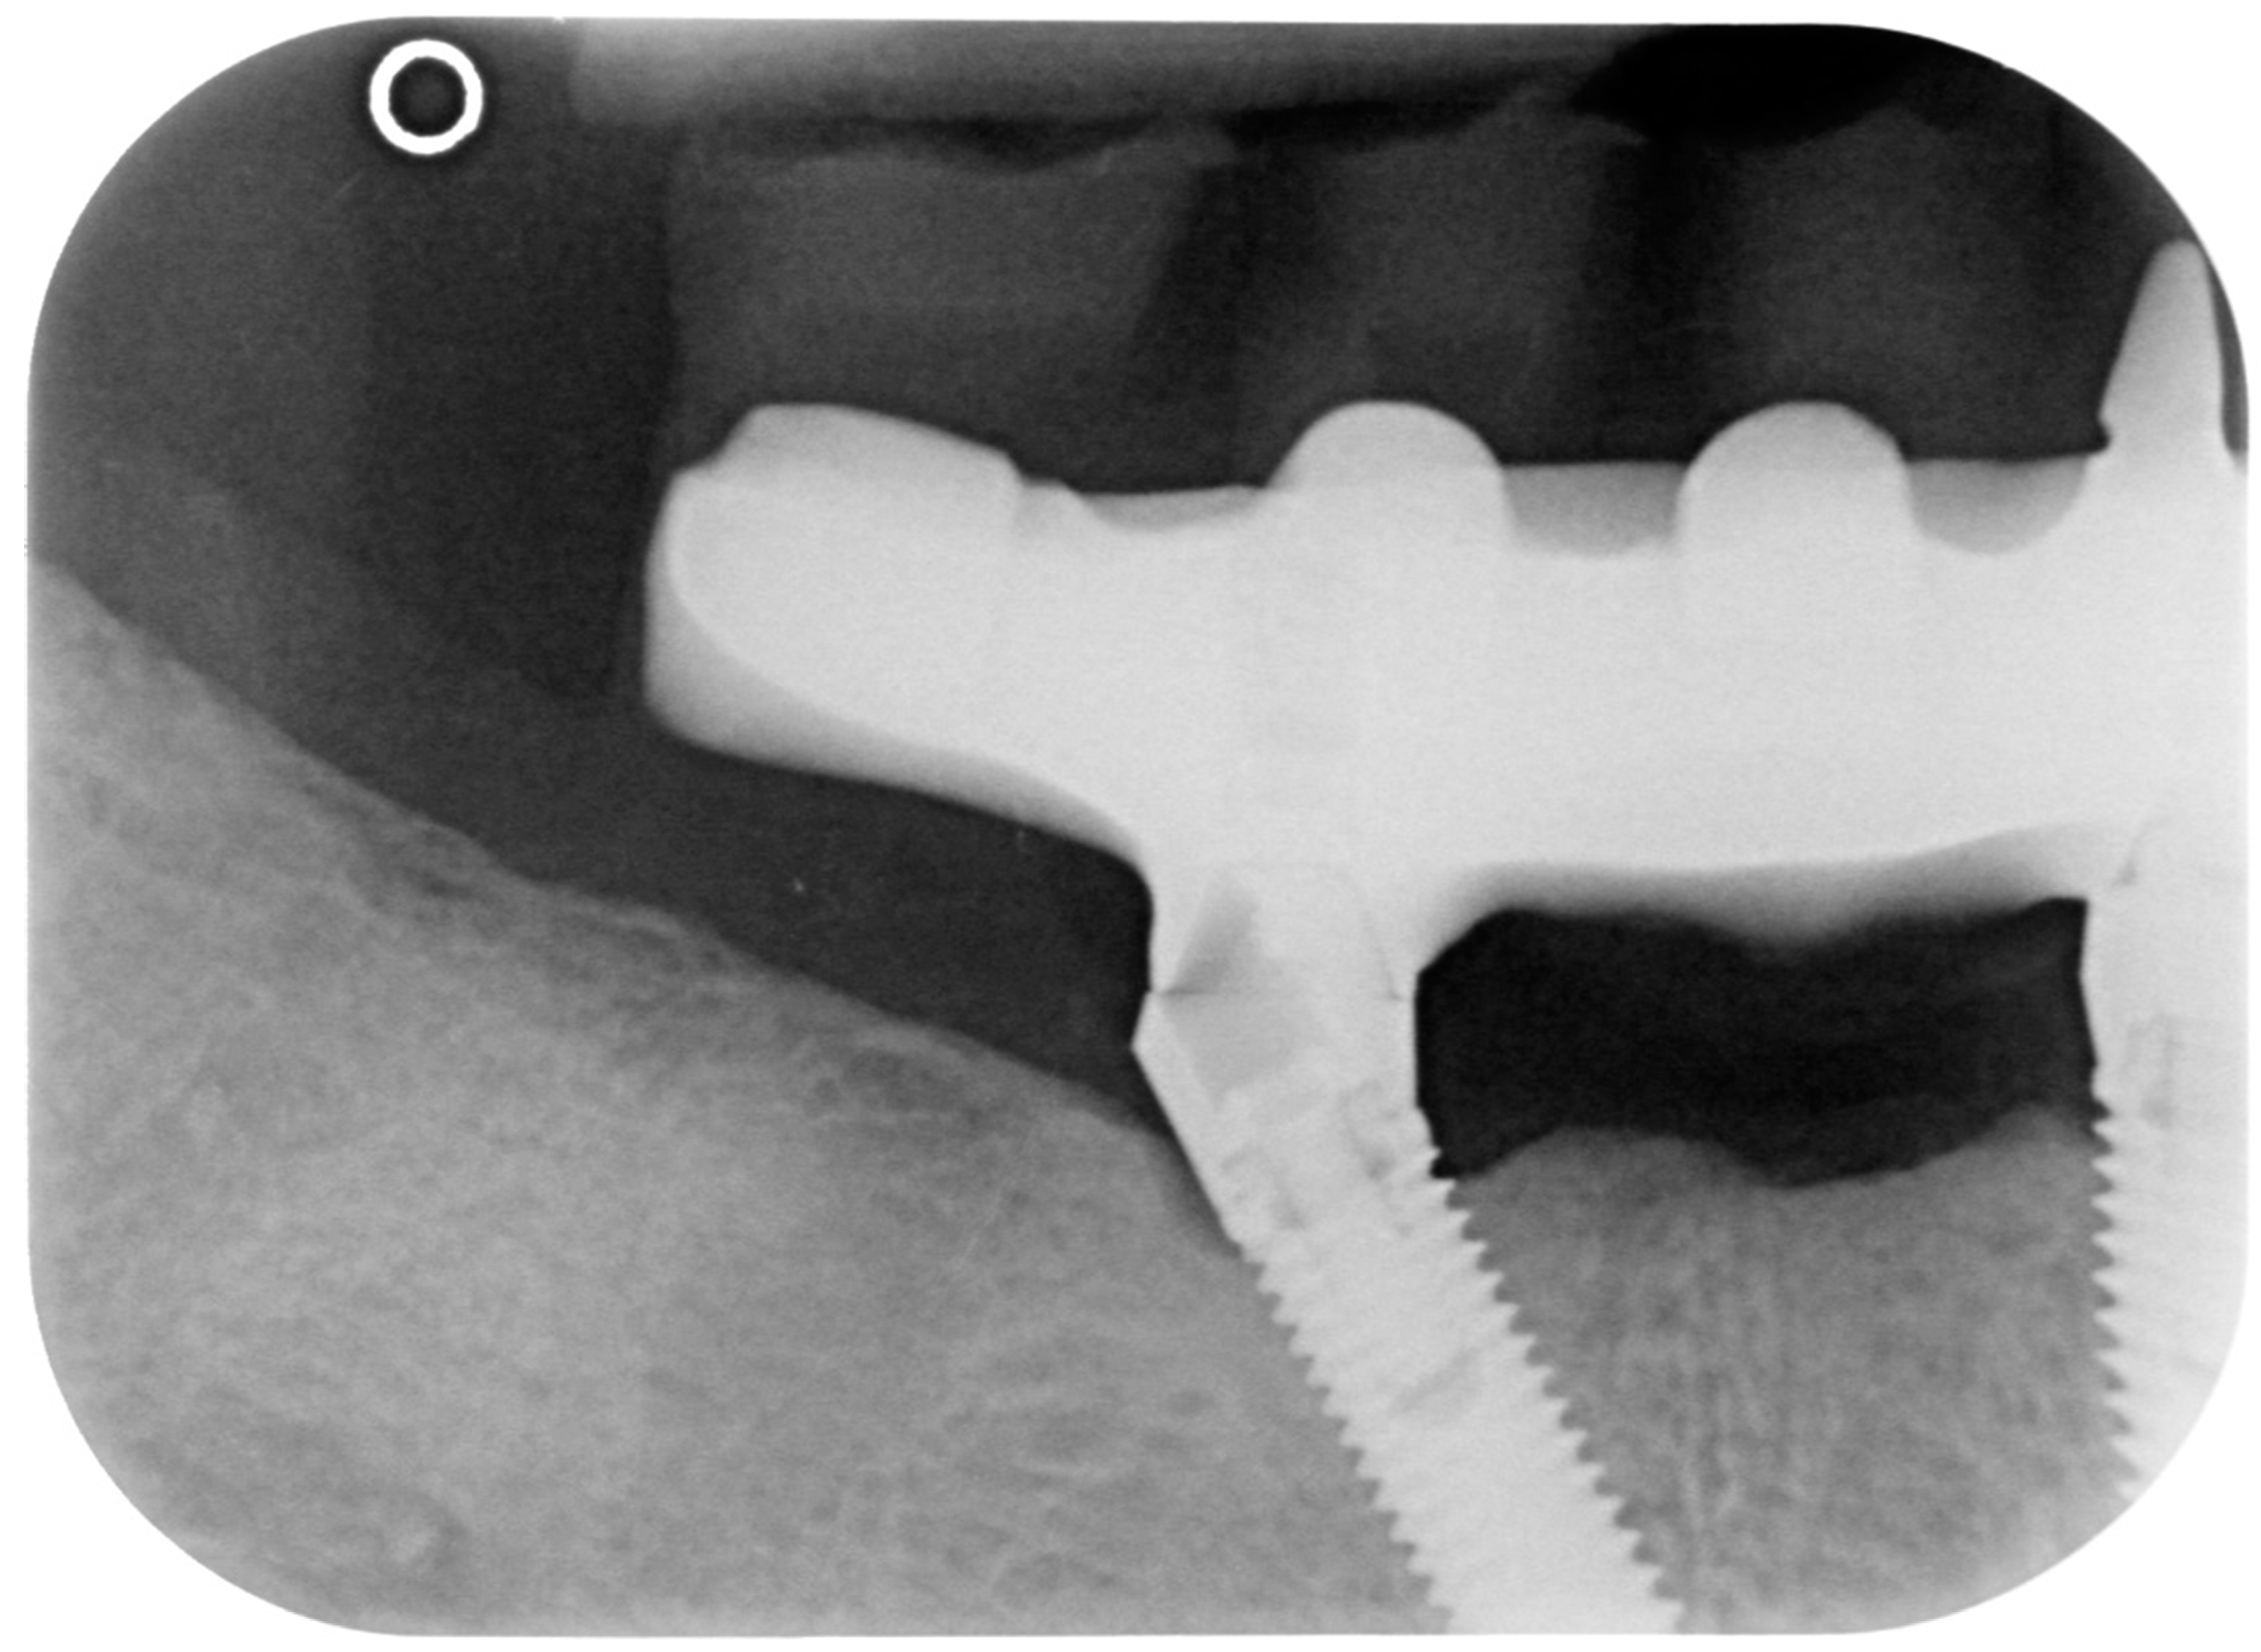

2.2. Case Report 2